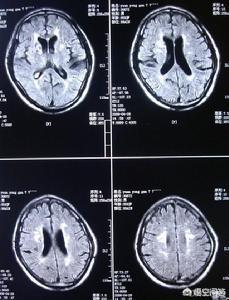

臨床的には、脳への血液供給不足が主な原因である。動脈硬化画像診断では、多くの場合、多発性瘢痕を呈する。虚血"!

(注:MRI画像では"ホワイトパッチ")